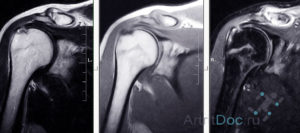

Головка плечевой кости пораженная артритом.

- воспалительные очаги, деструктивно-дегенеративные изменения костей и гиалиновых хрящей визуализируются в виде интенсивно окрашенных областей;

- на воспаление указывают сформировавшиеся вокруг тканей полости;

- доброкачественные и злокачественные новообразования выглядят, как участки с более плотной структурой. Они интенсивно окрашены и локализованы на границе между костями и мышцами;

- при разрыве связок заметно смещение оторванных частей в суставную полость;

- разросшиеся края костных пластинок и обызвествленные области сигнализируют о необратимом разрушении хрящевых тканей, развитии остеоартроза;

- полное или частичное сращивание суставной щели указывает на анкилоз (неподвижность сочленения) и необходимость хирургического вмешательства;

- образование секвестров (омертвевших тканей) является характерным признаком инфекционного артрита;

- скопление жидкости в синовиальной сумке указывает на бурсит, а наличие выпота в полости сустава — на синовит;

- изменения теплообмена, также определяемые при обследовании, сопутствуют многим заболеваниям плечевого сустава.

Во время расшифровки результатов оценивается состояние костных поверхностей, выстланных хрящевыми тканями. В норме на них не должно быть выраженных дефектов. Исследуются и расположенные рядом с сочленением связки, сухожилия, нервные пучки, мышечные волокна. Изменения мягкотканных структур часто указывают на вялотекущий воспалительный процесс.